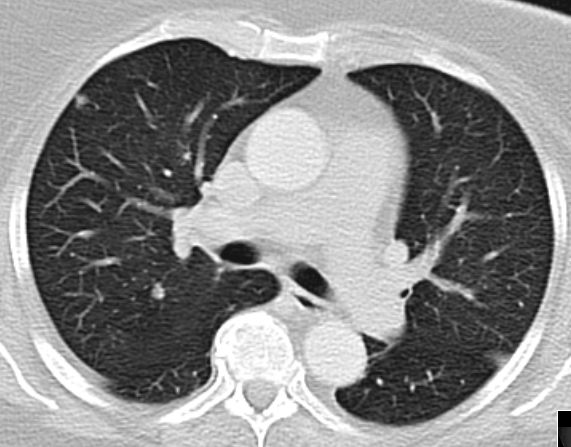

CT

61-jährige Frau mit Adipositas, Diabetes mellitus,  Hypertonie, Cholezystektomie. Vor 2 Jahren Vulva-Karzinom pT1b pN1b (1/24) M0 G2 . Vulvektomie rechts, Hemivulvektomie links mit, Sentinel-Lymphonodektomie inguinal bds. Vor 4 Monaten Lymphknotenmetastase links, R2 - Resektion, Bestrahlung abgelehnt. Jetzt progrediente Leistenmetastasierung.

Lungenmetastasen